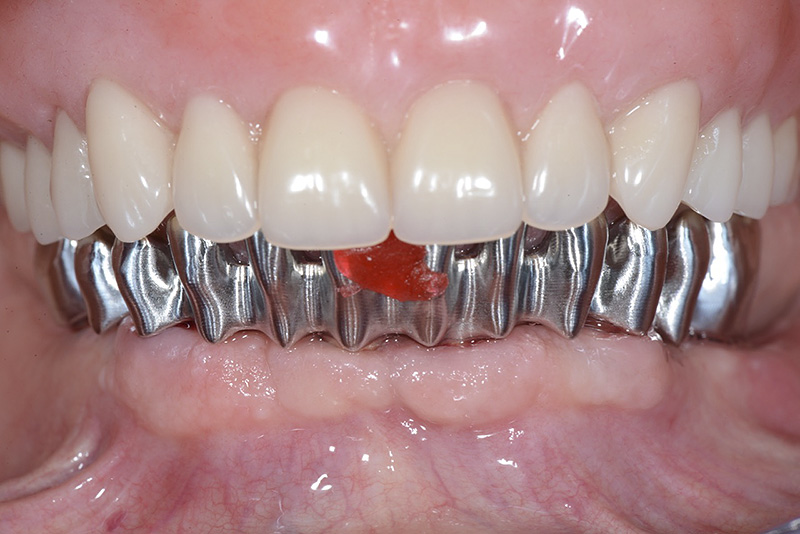

Vengono utilizzati 2 tipi di provvisori: il primo, cementato ai denti vicini, viene utilizzato dal momento dell’estrazione del dente fino ad impianto osteointegrato (circa 6 mesi); il secondo, avvitato direttamente all’impianto, ha una funzione di prova estetica ma soprattutto di guida per la maturazione dei tessuti gengivali peri-implantari portandoli verso la maturazione completa prima di posizionare la corona finale in disilicato di litio.